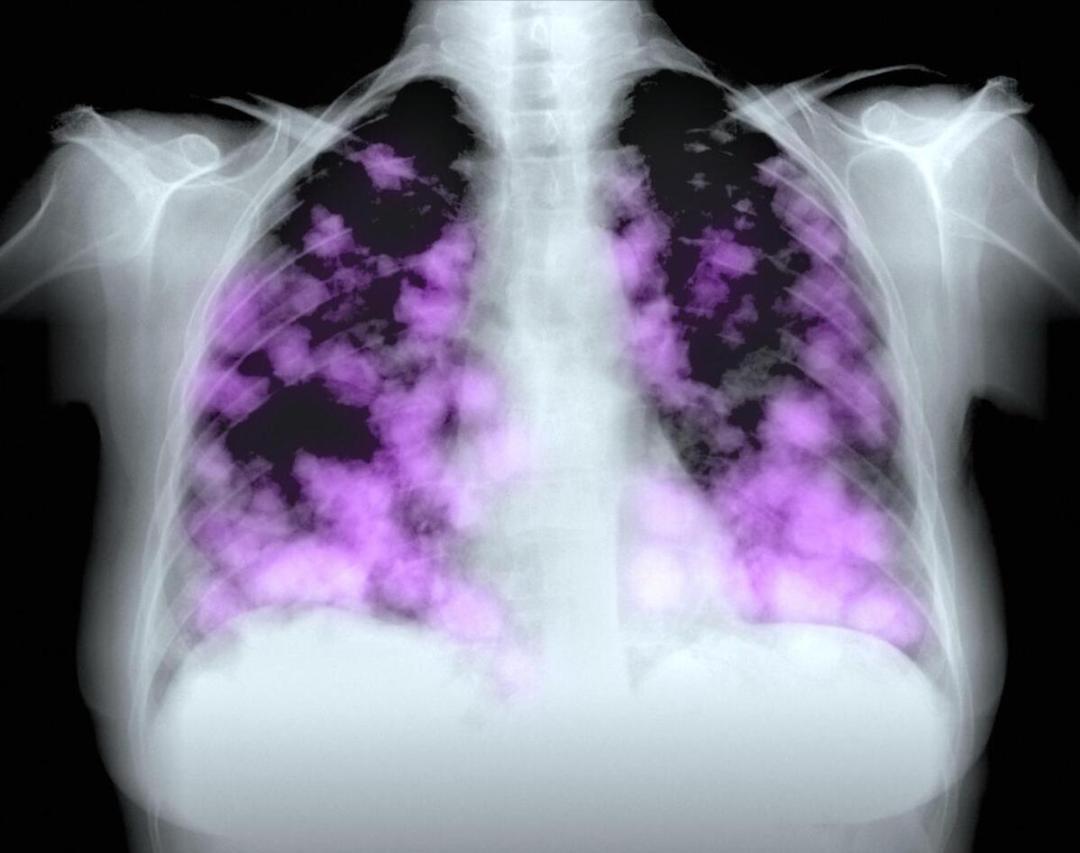

病人拿着报告吓坏了,感觉自己得了肿瘤,听了解释后虚惊一场。

原题:“病人拿着报告单吓坏了,感觉自己得了肿瘤,听了解释后虚惊一场”